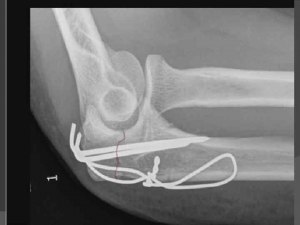

В каком случае при переломе устанавливаются спицы?

Спицы могут устанавливаться при переломе в следующих случаях:

1. Комплексный перелом: если перелом костей сложный и требует дополнительной стабилизации, врач может решить установить спицы для обеспечения более надежной фиксации и лучшего выравнивания костей.

2. Нестабильный перелом: если перелом сопровождается значительным смещением или нестабильностью костей, установка спиц может помочь предотвратить дальнейшее смещение и обеспечить лучшее заживление.

3. Многофрагментарный перелом: при наличии нескольких фрагментов перелома, спицы могут использоваться для соединения фрагментов и создания более устойчивой конструкции.

4. Открытый перелом: если перелом сопровождается разрывом кожи и наружным выступлением костей, установка спиц может помочь предотвратить инфекцию и обеспечить правильное заживление.

5. Положительный эффект: врач может принять решение установить спицы, если это обещает улучшить результаты лечения и ускорить процесс заживления.